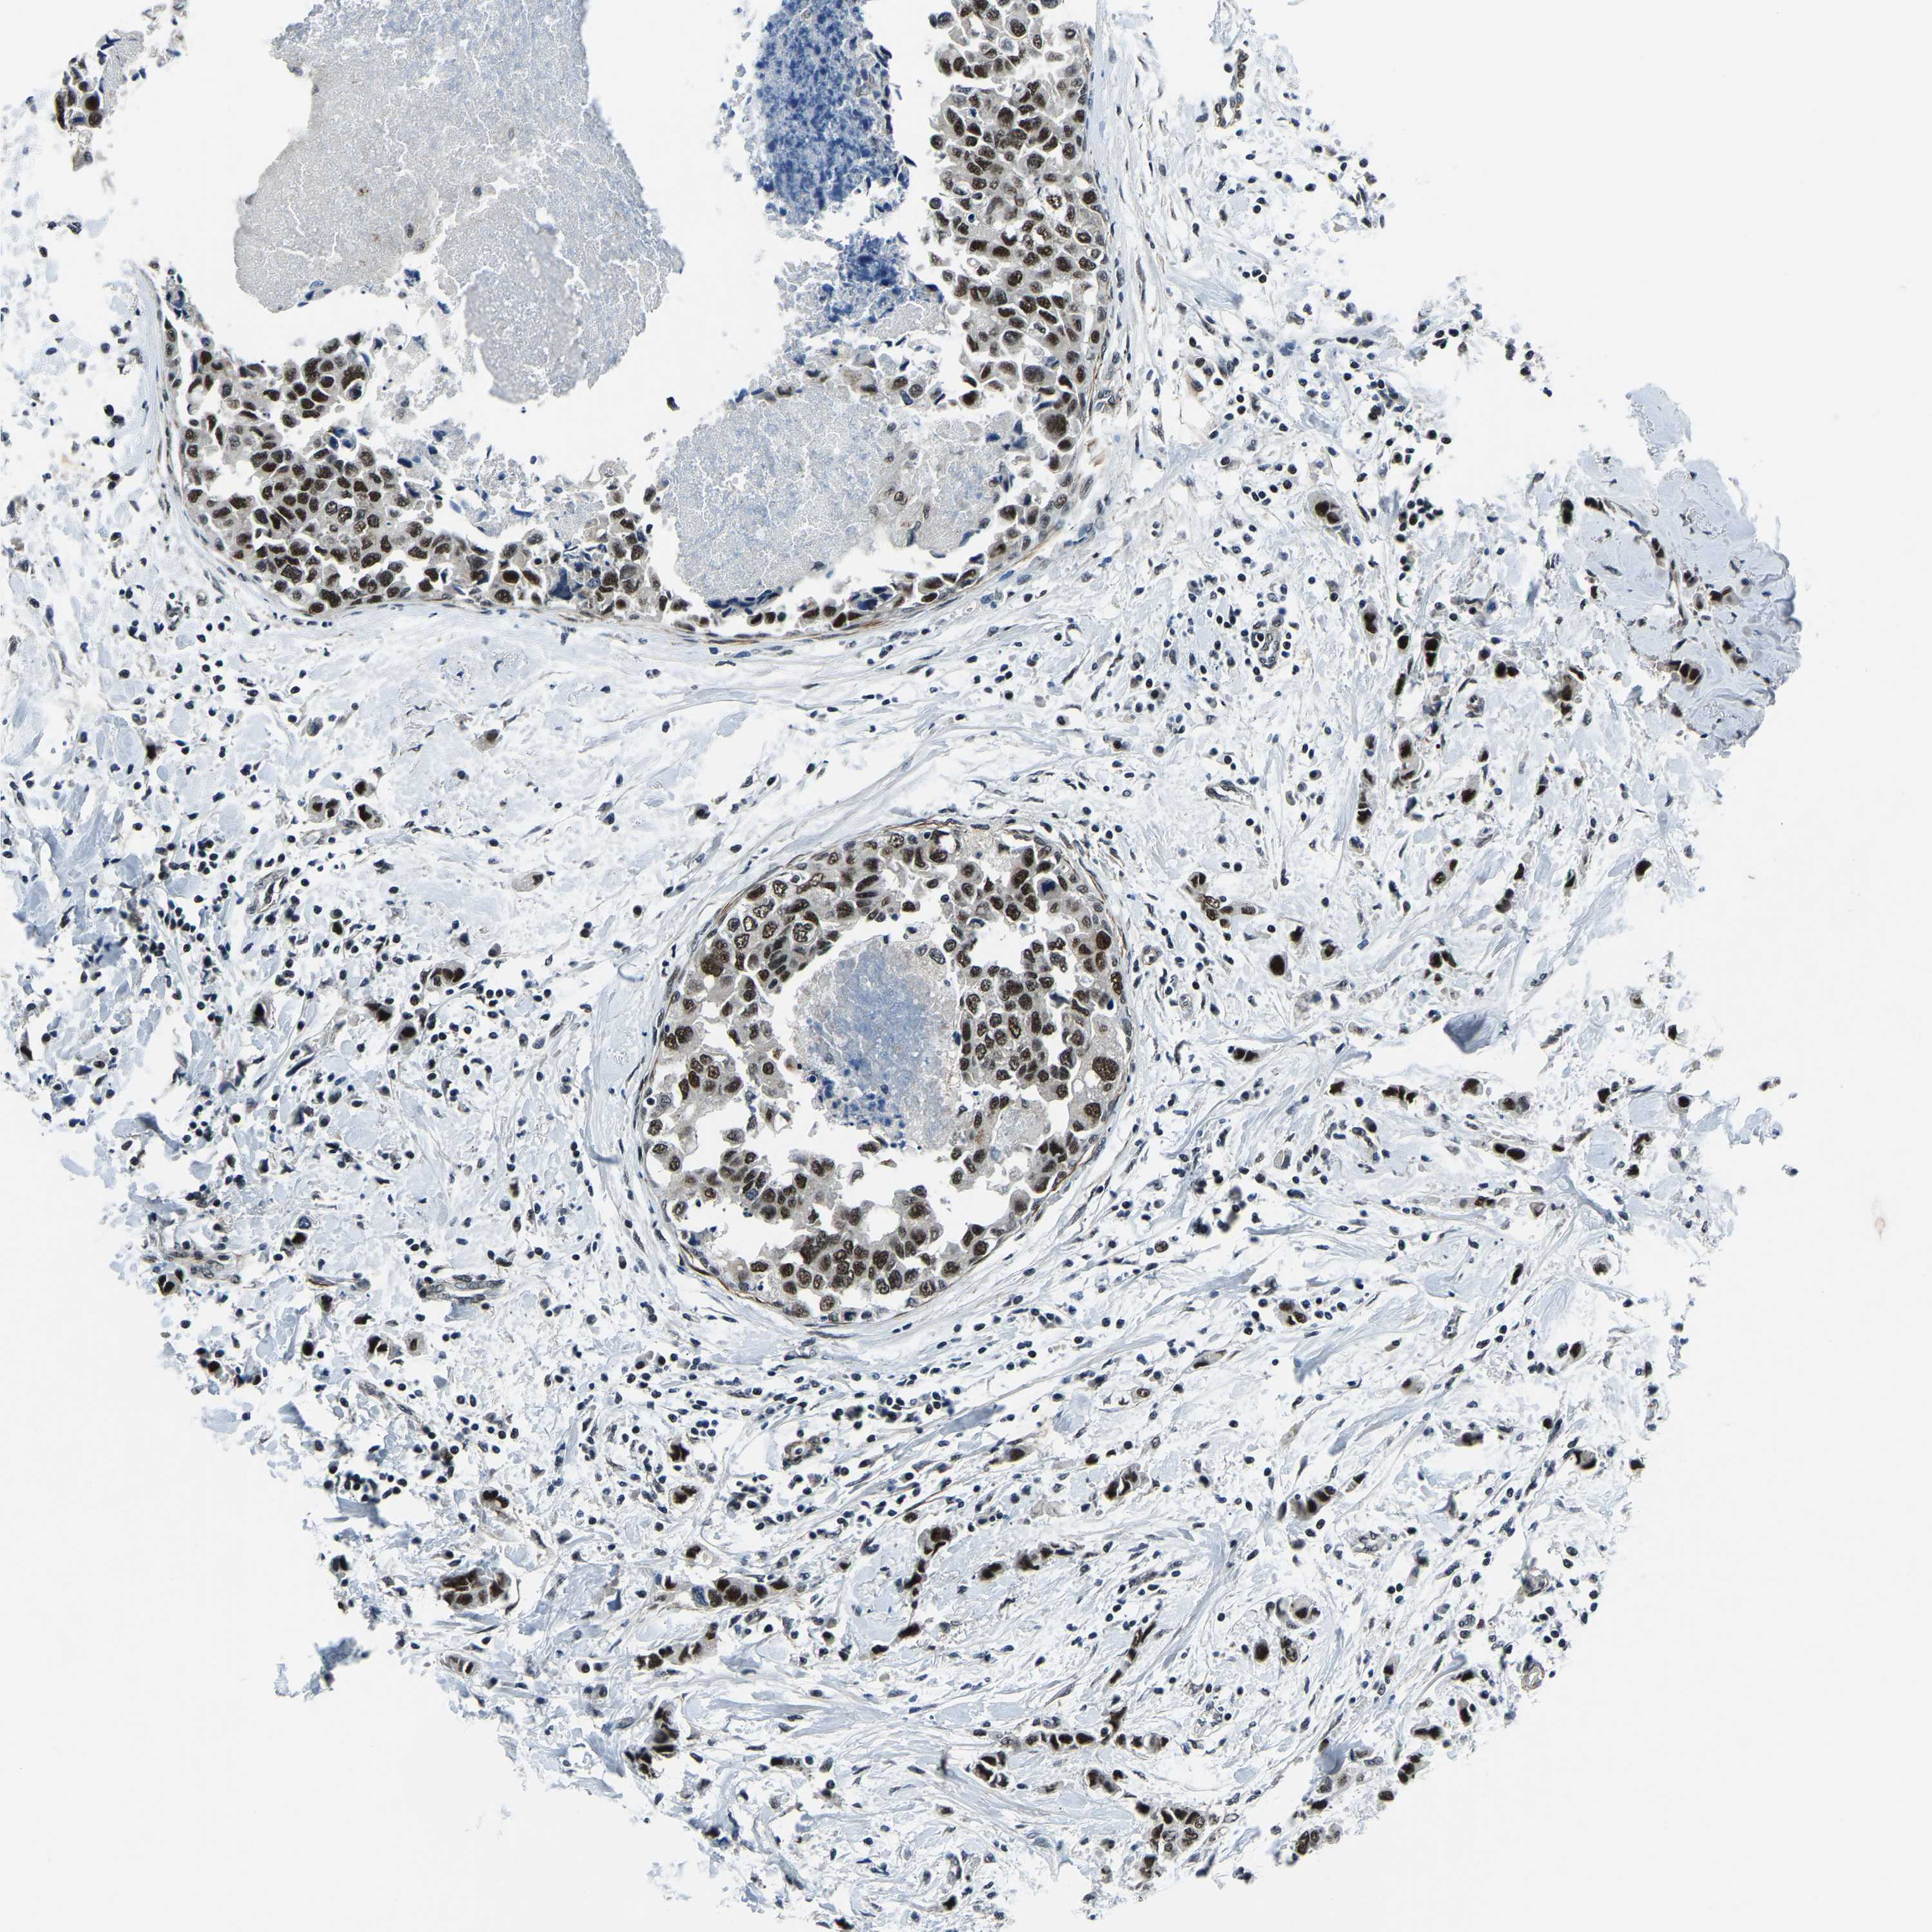

CANCER BREAST CANCER Show tissue menu

BRCA TCGA BRCA VALIDATION PROTEIN EXPRESSION